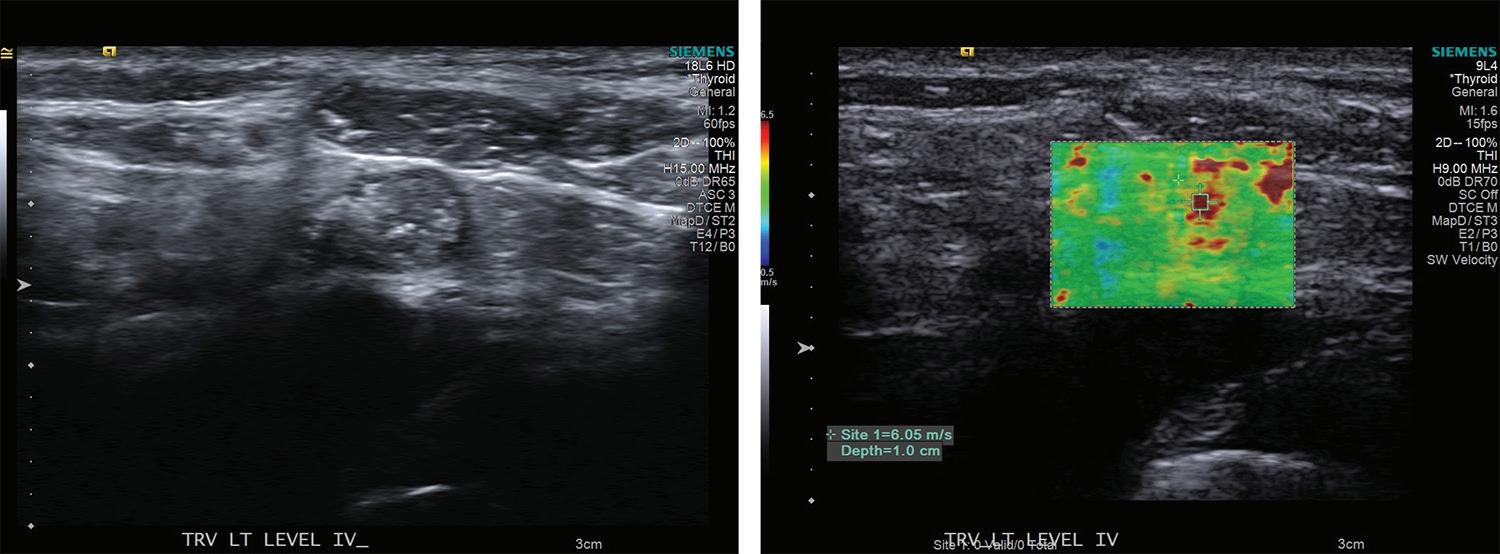

Volume 97, Number 1-2 www.entjournal.com 31 ORIGINAL ARTICLE

Additionally, diagnosis of lymph node invasion on presentation also serves as an important prognostic indicator for locoregional recurrence after the initial surgery.10,11

Approximately 30% of patients may develop recurrence following resection of primary disease, which is often associated with increased morbidity and mortality.12-14 PTC most often recurs or persists in cervical lymph nodes; therefore post-thyroidectomy surveillance with sonography of the neck and measurement of serum thyrogobulin level is required in the first 6 to 15 months and at regular intervals thereafter. The frequency with which patients are evaluated depends on serum thyroglobulin level and other risk factors.9

In evaluating recurrent disease, US findings have a reported sensitivity of 90%, specificity of 79%, and accuracy of 87.9%.8 The propensity of PTC for lymphatic spread and its effect on management of the disease underscores the need for accurate evaluation of cervical lymph nodes before and after thyroidectomy.

Elastography is a novel imaging modality that can be used clinically to assess elasticity of soft tissues. Elasticity is a parameter based on the strain or deformation of tissue in response to a physical force. Most malignancies reliably exhibit reduced elasticity and increased stiffness due to the nature of neoplastic growth, making this procedure a promising new development in the diagnosis of cancerous and metastatic foci.

The elastrography technique involves applying a force on the tissue and subsequently imaging the resultant deformation. This technique initially required the operator to physically push the transducer into the tissue to be examined, now termed quasi-static imaging. The unintended variable with

this technique was the differences in the degree of pressure applied by each observer. In efforts to increase objectivity and reproducibility, the acoustic radiation force impulse (ARFI) technique was developed, which involves emitting acoustic pulses inside tissue to generate micron-scale displacement.15

The distortion of tissues can be observed by ultrasonographic imaging, and areas of decreased strain can be recorded, creating a map of elasticity, known as an elastogram (figures 3 and 4). Additionally, whereas deformation can provide qualitative indications of tissue stiffness, measuring the speed of the shear wave, which is the speed with which the tissue wave travels perpendicularly from the pulse, can provide quantitative measurements of higher clinical value.16

Newer ARFI models can be used to measure shear wave velocity, which is inversely proportional to tissue elasticity, providing a means of numerical data collection.17 Supersonic shear imaging (SSI) or shear wave elastography (SWE) combines the technology of an applied ultrasonographic beam with ultrafast US imaging to create real-time, quantitative maps of tissue stiffness.18 Many newer models of US machines now have ARFI and/or SSI/SWE-based capabilities.

Review of literature